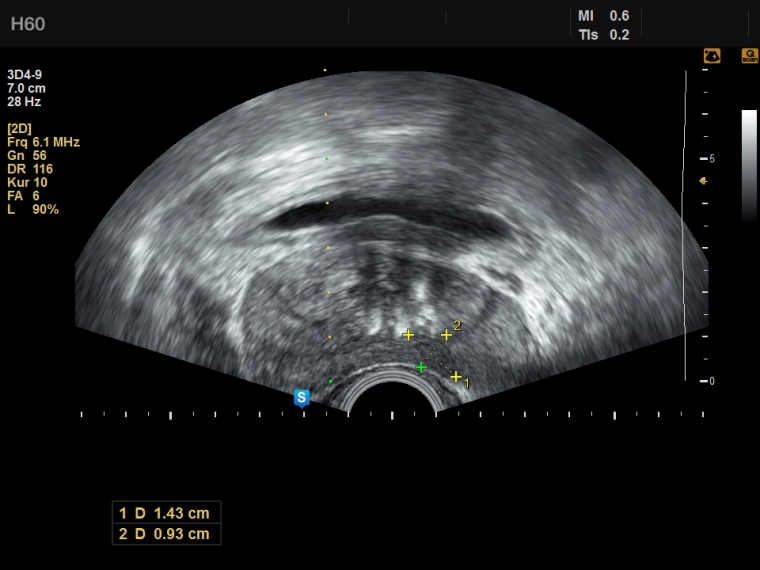

Prostatakrebs gehört zu den häufigsten Krebserkrankungen des Mannes. Die definitive Diagnose erfolgt mittels einer transrektalen oder transperinealen Prostatabiopsie und anschließender pathohistologischer Untersuchung. Eine präzise Diagnose erfordert eine exzellente gezielte Biopsie.

Welche Möglichkeiten eine elastische MRT-3D-TRUS Fusion mit dem Samsung-Ultraschallsystem H60 und der Urostation im praktischen Einsatz bietet, erläutert Priv.-Doz. Dr. Lars Budäus vom Prostatakrebszentrum der Martini-Klinik und des Universitätsklinikums Hamburg-Eppendorf.

Dr. Lars Budäus: Gerade in der Re-Biopsie nach unauffälliger Erstbiopsie und bei weiter steigendem PSA-Wert hilft die MRT-

Ultraschallfusionsbiopsie häufig, relevante Tumoren in atypischen Lokalisationen außerhalb der Areale, die in der randomisierten Biopsie untersucht wurden, zu detektieren. Dies konnte in einer aktuellen Studie zur Auswertung der diagnostischen Wertigkeit des MRTs und der randomisierten zwölffach Biopsie sowie in weiteren umfangreichen multizentrischen Studien gezeigt werden.

Dr. Lars Budäus: Die MRT-3D-TRUS Fusions-biopsie bietet gerade jungen Patienten mit dem klinischen Verdacht auf das Vorliegen eines okkulten, d. h. bisher noch nicht detektierten Tumors durch einen steigenden PSA-Wert und Patienten in der aktiven Überwachung im Rahmen der Re-Biopsie ein höheres Maß an diagnostischer Genauigkeit im Vergleich mit der Standardbiopsie.